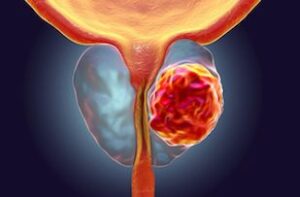

Une étude internationale menée par le centre Cedars-Sinai de Los Angeles révèle qu’associer deux traitements existants permet de diminuer de manière spectaculaire le risque de décès lié au cancer de la prostate. Cette avancée, saluée par la communauté médicale, ouvre la voie à une nouvelle stratégie thérapeutique pour les formes les plus agressives de la maladie.

L’essai clinique, conduit pendant huit ans sur plus de 1 000 patients issus de dix-sept pays, a comparé trois groupes : l’un traité avec de l’enzalutamide, l’autre avec du leuprolide, et un troisième recevant la combinaison des deux médicaments. Ces traitements, déjà approuvés séparément par la Food and Drug Administration américaine, sont couramment prescrits pour freiner la progression des tumeurs prostatiques. Les résultats, publiés par l’équipe du Dr Stephen Freedland, montrent que la combinaison des deux molécules réduit le risque de décès de 40,3 % par rapport aux traitements administrés seuls. Une découverte d’autant plus prometteuse que près de 40 % des hommes traités initialement par chirurgie ou radiothérapie voient leur cancer réapparaître sous une forme plus agressive.

Le professeur Hyung Kim, urologue oncologue et président du département d’urologie du Cedars-Sinai, estime que cette étude « va changer la manière de traiter les patients atteints de cancers de la prostate agressifs ». Selon lui, cette approche combinée « prolonge la survie et améliore la qualité de vie, sans nécessiter la mise au point de nouveaux médicaments ». L’intérêt de cette découverte réside aussi dans sa rapidité d’application possible. Les deux traitements étant déjà homologués, leur usage combiné pourrait être autorisé rapidement, évitant les longues phases de validation nécessaires à la mise sur le marché d’un nouveau produit. Avec plus de 50 000 nouveaux cas chaque année en France, le cancer de la prostate demeure le plus fréquent chez l’homme. Cette avancée scientifique pourrait donc marquer une étape majeure dans la lutte contre une maladie qui reste, malgré les progrès, l’une des premières causes de mortalité masculine liée au cancer.